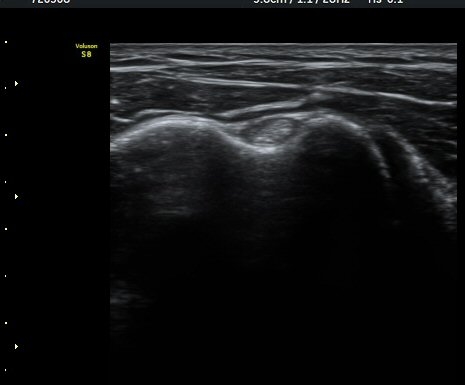

¼ö¾×Àú·ù°¡ °üÂûµÈ´Ù(±×¸² 1, 2). °ß°©ÇÏ±Ù°Ç Á¾´Ü¸é°Ë»ç¿¡¼­ °ß°©ÇϱٰÇÀÇ °üÀý³»ºÎÀ§(±×¸² 3)

¿Í ¼Ò°áÀý »óºÎ(±×¸² 4)¿¡¼­ ƯÀÌ ¼Ò°ßÀ» º¸ÀÌÁö ¾Ê´Â´Ù.